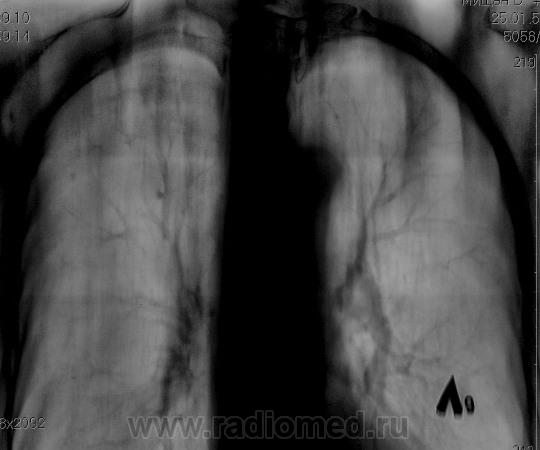

По томограммам не понятно что хотели получить? Интересовали эти маленькие плотные очаги?

Справа на верхушке инфильтративная тень. Слева в задних отделах мелкие буллы.

На последнем срезе тень в 1 сегменте, мелкие полости в верхних долях с обеих сторон.